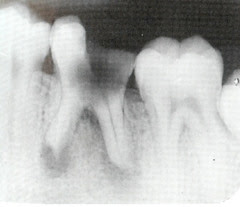

The most common types of recurring tooth pains are: Sporadic sharp stabbing pains This stabbing pain usually accompanies chewing, eating cold or hot foods, or simply opening your mouth. In fact, it can often be seen on a dental x-ray situated above the molar and pre-molar teeth in the upper jaw. Because of this, it allows for easy spread of infection.

Pericoronitis is often associated with partially erupted and impacted mandibular third molars (lower wisdom teeth), often occurring at the age. However, the root-filled tooth and the root canal(s) have already undergone a variety of treatment procedures, including use of mechanical instruments such as burs, and files, local disinfecting agentssuchasirrigants,andinter-appointmentdressings and root filling. The main causes of dental abscesses are tooth decay and trauma. With regular tooth decay, small cavities can lead to big problems if they go untreated.